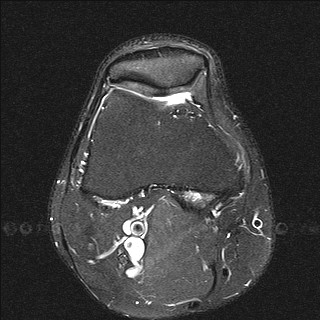

Способ проиллюстрирован чертежами, поясняющими сущность и эффективность заявляемого способа. На фиг.1 - оперативный доступ к сухожилию длинной малоберцовой мышцы в области наружной лодыжки; на фиг.2 - чрезоперативный доступ, теновыделителем проксимально отсекают сухожилие длинной малоберцовой мышцы от мышечного брюшка и выводят сухожилие в область операционной раны; на фиг.3 - отсеченное сухожилие длинной малоберцовой мышцы на препаровочном столике; на фиг.4 - схематично представлено направление проведения каналов, сухожилия и его крепление интерферентными шурупами в мыщелках большеберцовой и бедренной костях, трансоссальная фиксация в головке малоберцовой кости;

на фиг.5 - рентгенограмма коленного сустава в прямой и боковой проекции больного с начальными признаками остеоартроза; на фиг.6 - магнитно-резонансная томография коленного сустава больного, где отсутствует передняя крестообразная связка и наружная боковая связка; на фиг.7 - магнитно-резонансная томография коленного сустава больного, где показана восстановленная передняя крестообразная связка и наружная боковая связка; на фиг.8 - полное сгибание коленного сустава через три месяца после операции; на фиг.9 - стабильность коленного сустава через три месяца после операции.

На МРТ левого коленного сустава до операции в боковой и фронтальной проекциях - отсутствие ПКС и дефект НБС (Фиг.6).